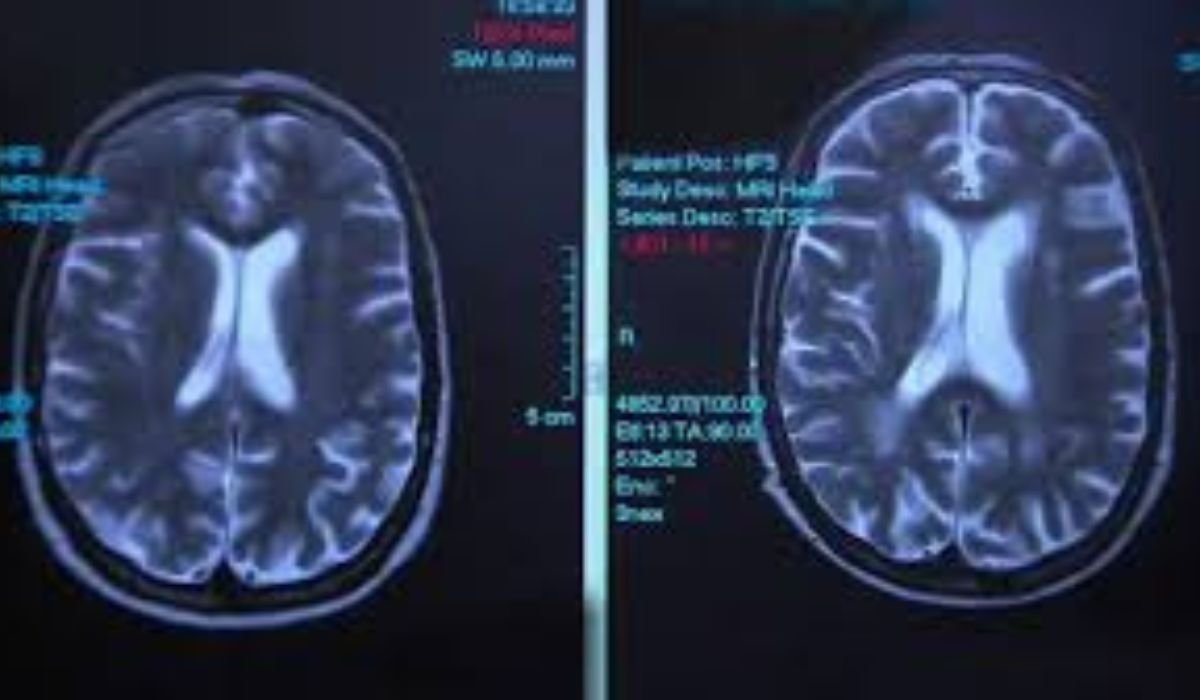

Brain is a delicate and complicated organ and regulates every thing we do- A MRI brain (Magnetic Resonance Imaging) forms a valuable diagnostic tool in providing us with accurate information of the structure and functions of brain.

The effects of alcohol on the brain plays an imperative role in the diagnosis and management of alcohol related disorders. The structural and functional changes that can be posed in the brain by alcohol can be identified in MRI scan at affordable cost.

MRI Brain, and What It Could Display

When alcohol is ingested it wets the brain and interferes with brain chemistry as well as neurotransmitters. Alcohol abuse may result in cognitive problems, which include memory loss, poor decision-making, and emotional ranging in chronic alcohol abuse. Such changes are visible by using neuroimaging methods such as Magnetic Resonance Imaging (MRI).

MRI scan images give clear details of the brain that also depicts the changes or distortions made by the consumption of alcohol. The smaller brain volume in various regions of the brain such as hippocampus, frontal, temporal and dilation of the sulcus can be seen using traditional MRI scan or Functional MRI (fMRI) scan that can be highlighted by the scan and include cortex responsible in decision making and lack of control over impulses impressions.

An even more elaborate test such as Functional MRI indicates the brain activity that is produced by the drinking of the alcohol. The changes may be noted in areas of normal neural activity affected as well as in areas of compensatory mechanisms that may be involved in order to compensate the alcohol damage to the brain.

MRI image scans are used to diagnose diseases such as alcohol-related brain damage (ARBD) and alcohol use disorder (AUD) in clinical practice. They aid orientation of clinicians on the extent of brain damage, intervention planning and tracking increase or restoration of brain functionality on a longitudinal process. In these interventions, it is imperative to understand the principles of neuroplasticity because it establishes a way through which strategies are formed to encourage brain recovery and help in improving cognitive restitution.

However, the entire process of diagnosing comprehensive images of brain problems related to alcohol involves a multidisciplinary approach as the use of the MRI scans is vital as a diagnostic tool. Better insights can be gained through integration of imaging evidence into clinical judgements, including neuropsychological methods and a clear patient history.

To sum up, MRI scans can prove to be precious in the diagnosis and perception of the effect of alcohol on the brain. They provide information on structural changes and functional changes that can help in early recognition, planning of treatment and monitoring of treatment success.